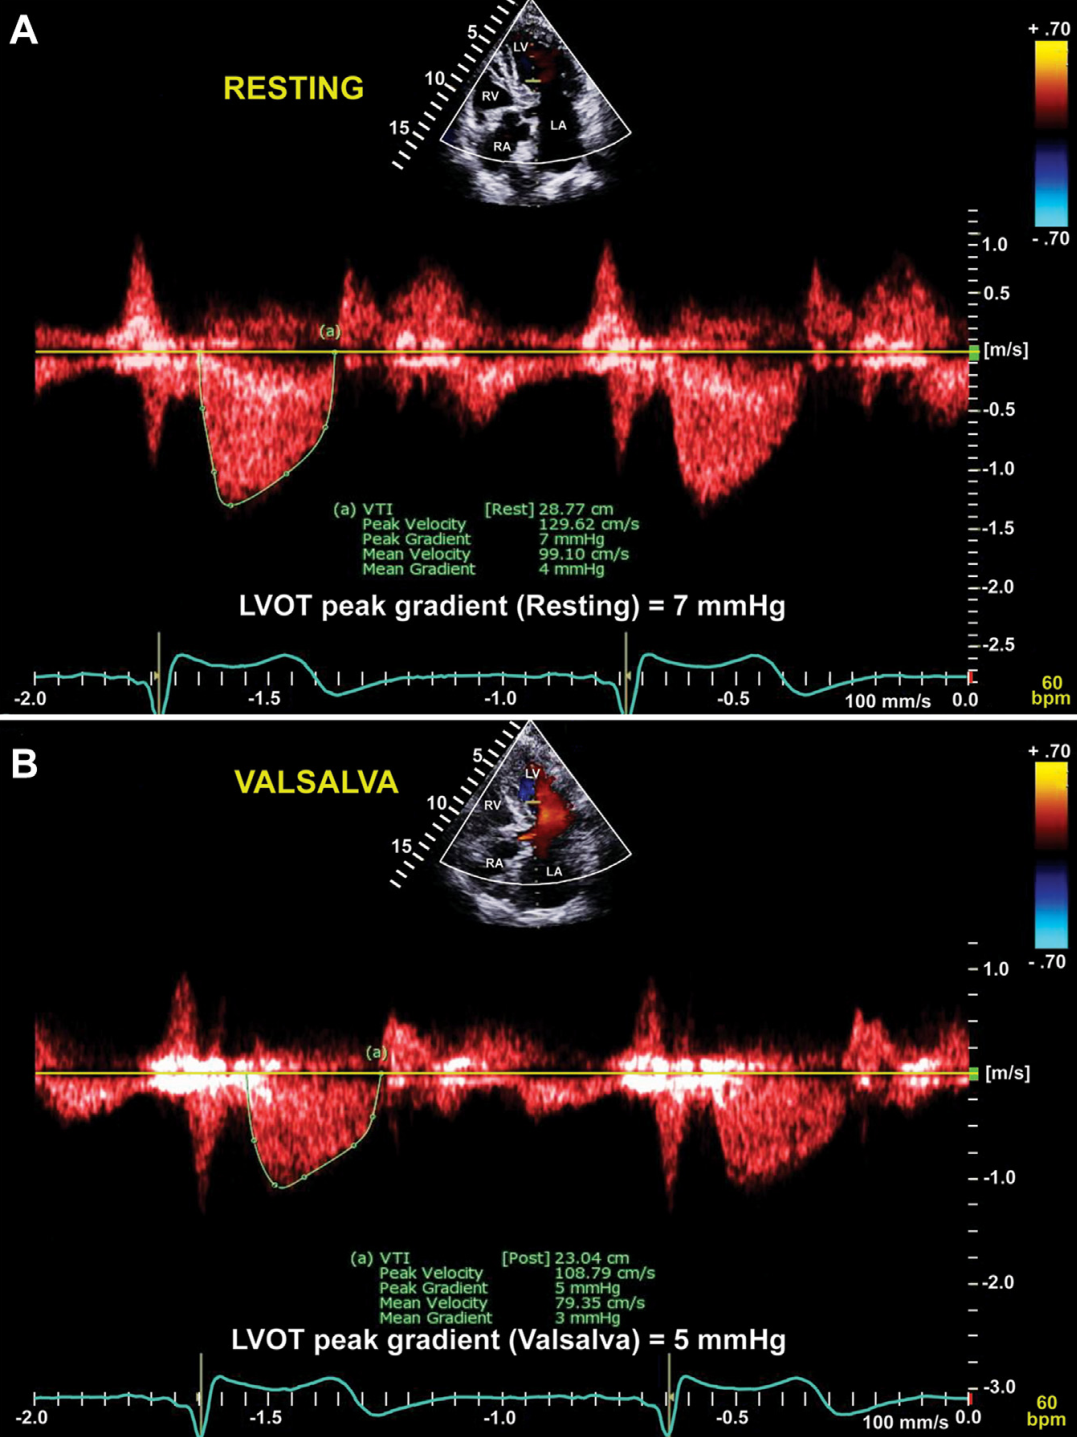

图7 3个月随访超声

静息LVOTO 7mmHg,ValsalvaValsalva动作 5mmHg。